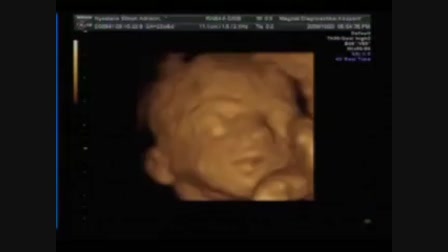

Kíra baba 2009.09.19-én született. A felvétel 2010.01.05-én készült... :-)